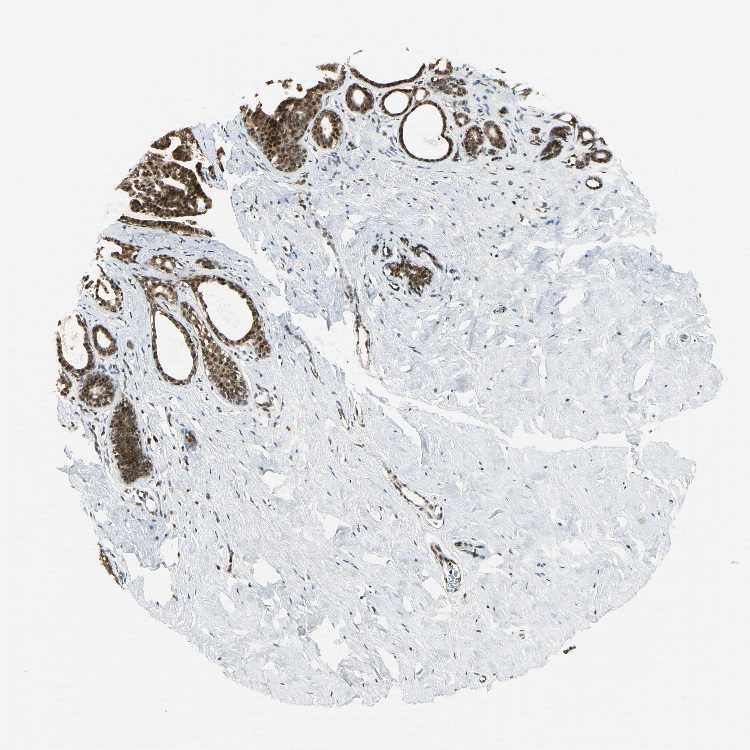

DAXX